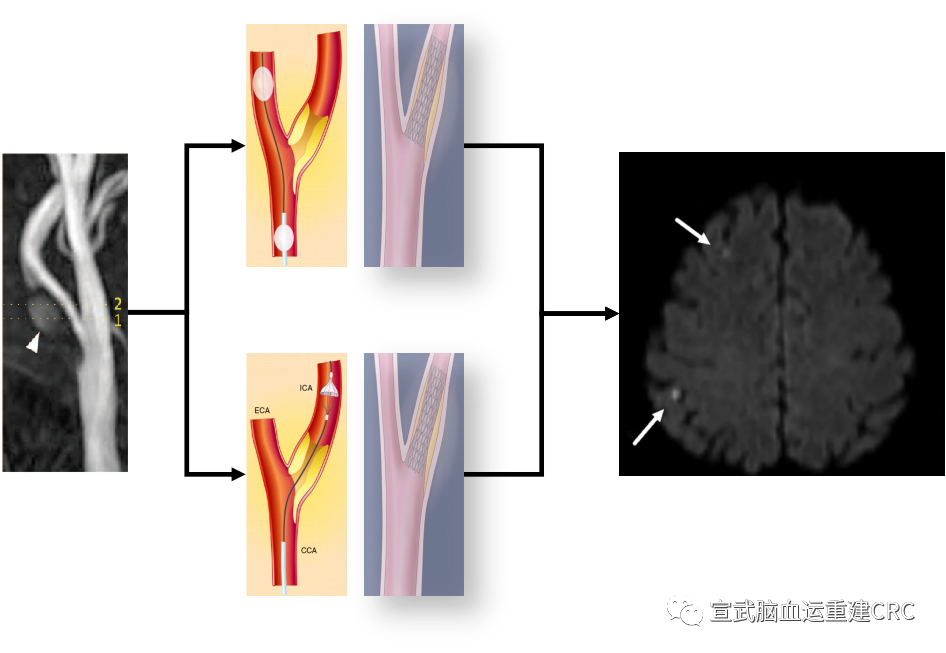

从朴素的角度,选择两种不同的栓塞保护装置,他们的原理不一样,远端的保护伞有他的问题,要先通过斑块再打开保护装置。但是近端的球囊MoMa的这个装置我们可以在不干扰斑块的情况下,阻断血流从根本上去解决这个问题。

于是我们就有一个假设,认为MoMa这个装置近端的保护装置的保护效力,要比远端的保护装置更好。就把MoMa选作为一个试验组,干预组。以Spider为代表的这种保护伞,定为一个对照组。

结局的选择:影像学新发梗死作为一个主要终点设计的这个试验。然后根据PICOS原则,推进试验。

治疗相关的问题更合适设计随机对照试验,来实现临床证据的获取。

以我们设计的框架即想要的病人收进来随机分成两组。一组用MoMa一组用Spider。最后通过指标来判定哪个更好。

Composite outcome of any stroke, death, or MI within 30 days was 8.1% (13/160) in the IPH group and 2.1% (5/239) in the non-IPH group (p<0.01)

The rate of postoperative infarct on DWI was 49.7% (75/161) for the IPH group and 33.6% (81/ 241) for the non-IPH group (OR=2.01, 95% CI 1.31 to 3.09, p<0.01).

主要研究终点:术后7天内,同侧DWI新发梗死灶发生率。

次要研究终点:

围术期卒中、急性心梗、死亡等严重不良事件;

术后任何出血事件、急性肾功能损伤等手术相关并发症;

术后7天,同侧DWI新发梗死的数量、体积和部位;

术后7天,对侧DWI新发梗死的数量、体积和部位;